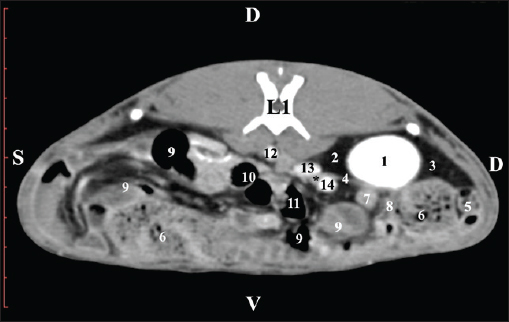

Fig. 3. Pre-contrast computed tomography (CT) anatomical scan of regio abdominis cranialis at the L1 level. (1) Medulla renis; (2) cortex renis; (3) pelvis renalis; (4) lobus caudatus (proc. caudatus) with visceral adipose tissue; (5) ureter; (6) pars descendens of the duodenum; (7) jejunum; (8) cecum; (9) colon ascendens; (10) lien; (11) colon descendens; (12) colon transversum. At the L2 level, the right kidney was in contact with the liver’s proc. caudatus, pars descendens of the duodenum, and the ileum. Pelvis renalis was a distinct hypoattenuated funnel-shaped soft tissue finding, whose narrow end pointed at the renal hilum and passed into the ureter. Recessus renalis was a clearly visible hypoattenuated widening of the central part of the renal pelvis in the dorsal and ventral directions (Figs. 4 and 5).

Fig. 4. Pre-contrast CT anatomical scan of the regio-abdominis media at the cranial L2 edge level. (1) Ren dexter; (2) pelvis renalis; (3) lobus caudatus (proc. caudatus) with visceral adipose tissue; (4) pars descendens of the duodenum; (5) ileum; (6) jejunum; (7) colon ascendens; (8) cecum; (9) colon transversum; (10) colon descendens; (11) lien; (12) pars transversa of the duodenum ; (*) ureter; (white arrow) recessus renalis.